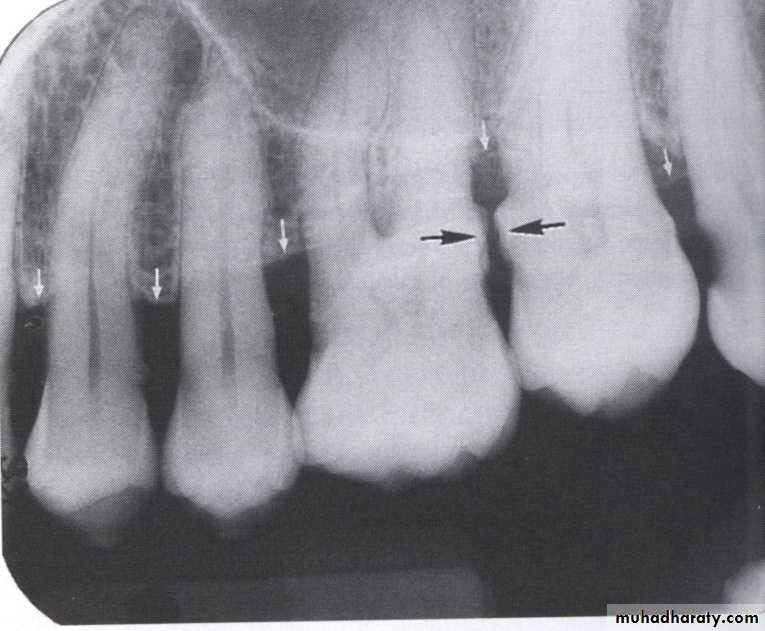

Direction :

Intercrestal bone should be parallel with line dawn from the CEJ of one tooth to that of the contacting tooth.

1. Horizontal bone loss:- When loss occurs on a plane that is parallel with a line drown.

2.Vertical bone loss:- when there is greater bone loss in one tooth than on the adjacent tooth, so the bone level is not parallel with a line joining the CEJ.